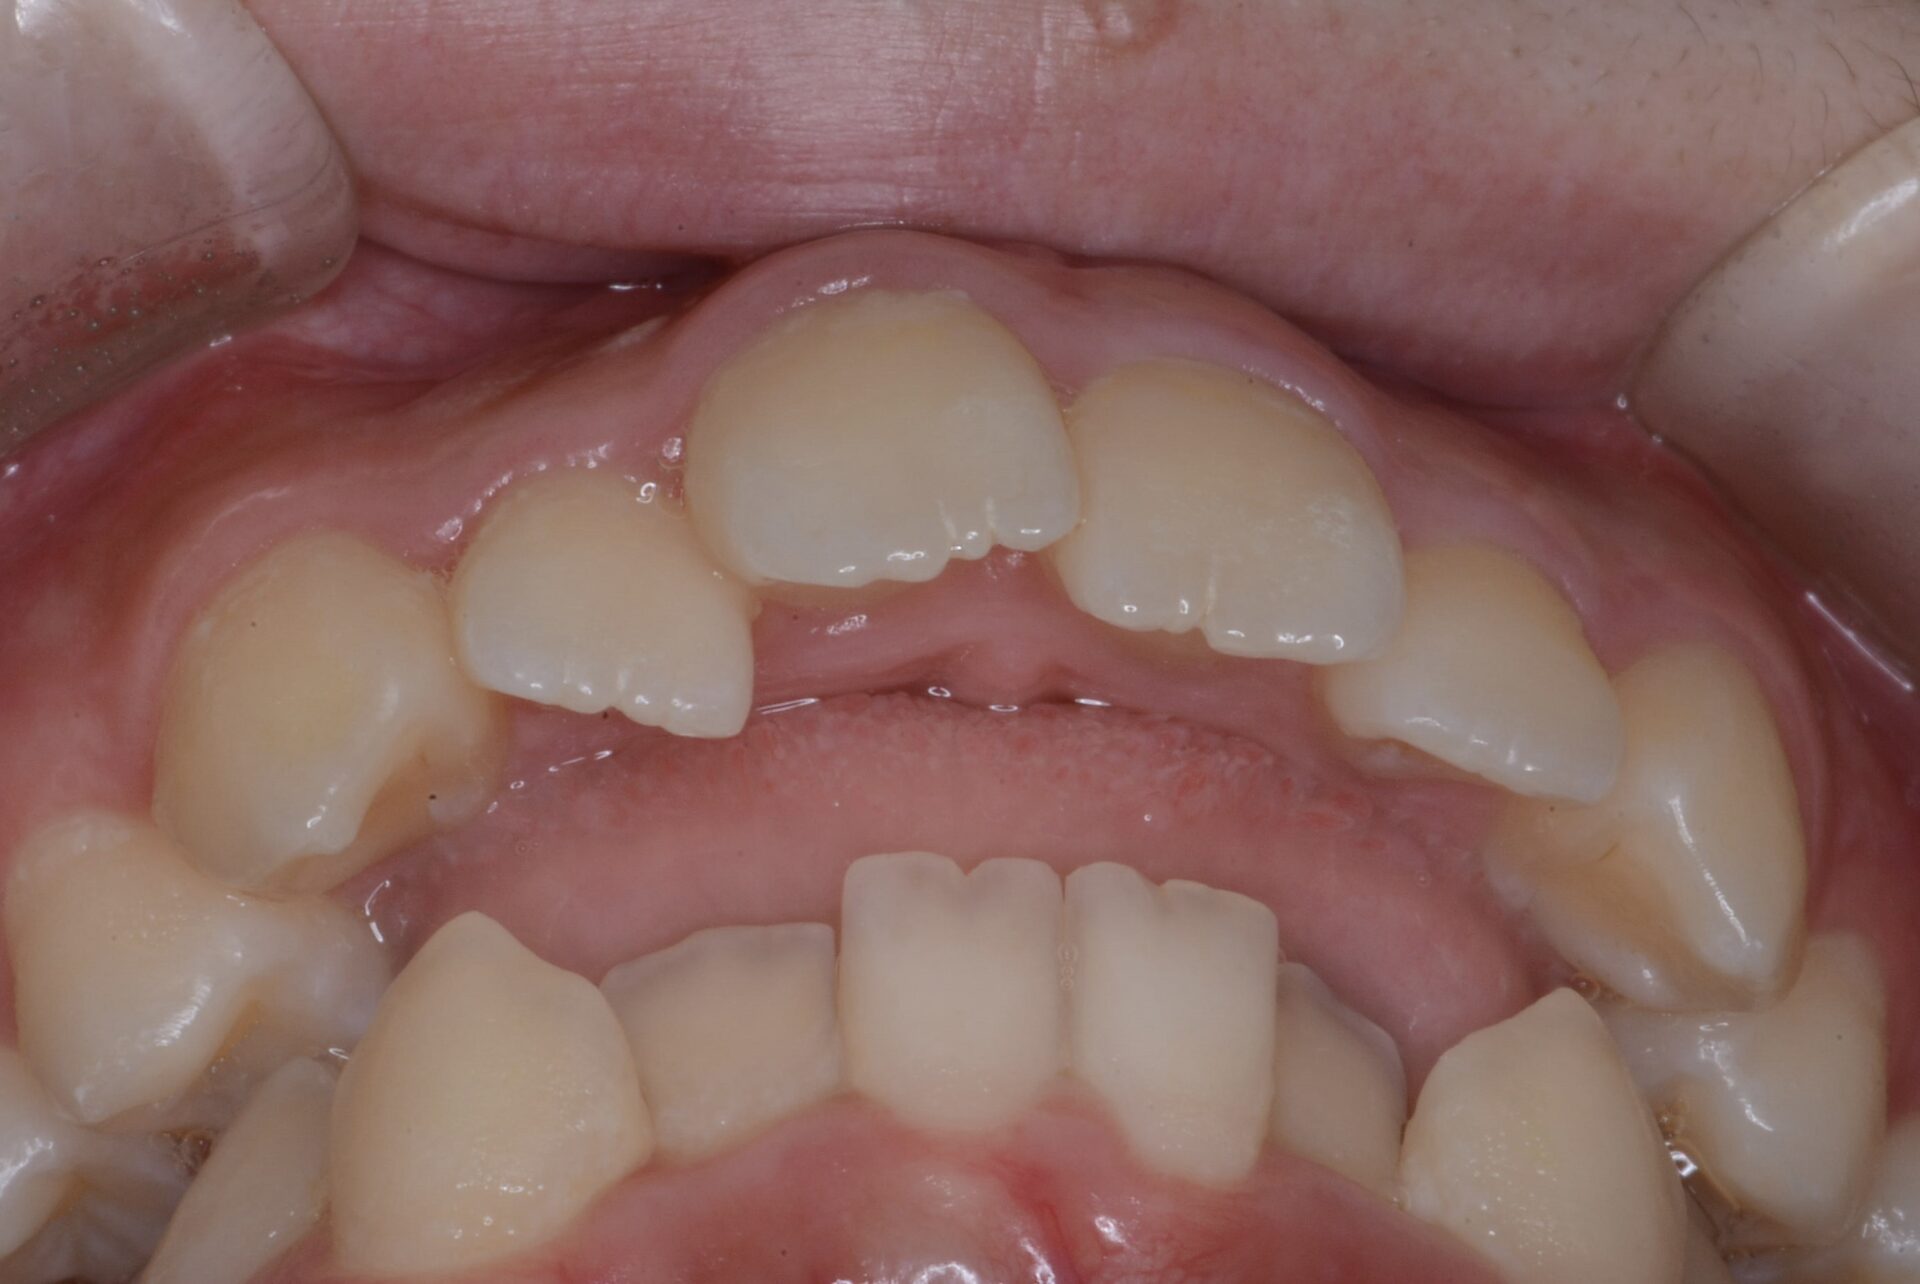

2016年 9歳 (上顎)

上顎口蓋の幅は小さくない。

2023年 16歳 下方から見ると前歯は全くかめていない。